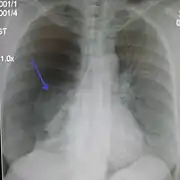

Chest X-ray

A plain chest radiograph, ideally with the X-ray beams being projected from the back (posteroanterior, or "PA"), and during maximal inspiration (holding one's breath), is the most appropriate first investigation.[30] It is not believed that routinely taking images during expiration would confer any benefit.[31] Still, they may be useful in the detection of a pneumothorax when clinical suspicion is high but yet an inspiratory radiograph appears normal.[32] Also, if the PA X-ray does not show a pneumothorax but there is a strong suspicion of one, lateral X-rays (with beams projecting from the side) may be performed, but this is not routine practice.[15][19]

Chest X-ray showing a pneumothorax on the right (left in the image), where the absence of lung markings indicates that there is free air inside the chest

Chest X-ray showing the features of pneumothorax on the left side of the person (right in image)

It is not unusual for the mediastinum (the structure between the lungs that contains the heart, great blood vessels, and large airways) to be shifted away from the affected lung due to the pressure differences. This is not equivalent to a tension pneumothorax, which is determined mainly by the constellation of symptoms, hypoxia, and shock.[13]

The size of the pneumothorax (i.e. the volume of air in the pleural space) can be determined with a reasonable degree of accuracy by measuring the distance between the chest wall and the lung. This is relevant to treatment, as smaller pneumothoraces may be managed differently. An air rim of 2 cm means that the pneumothorax occupies about 50% of the hemithorax.[15] British professional guidelines have traditionally stated that the measurement should be performed at the level of the hilum (where blood vessels and airways enter the lung) with 2 cm as the cutoff,[15] while American guidelines state that the measurement should be done at the apex (top) of the lung with 3 cm differentiating between a "small" and a "large" pneumothorax.[33] The latter method may overestimate the size of a pneumothorax if it is located mainly at the apex, which is a common occurrence.[15] The various methods correlate poorly but are the best easily available ways of estimating pneumothorax size.[15][19] CT scanning (see below) can provide a more accurate determination of the size of the pneumothorax, but its routine use in this setting is not recommended.[33]